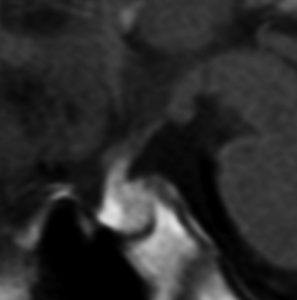

8歳で身長の伸びが悪くなり3年間診断されませんでした。12歳時に軽度の尿崩症を併発して発見されたものです。下垂体前葉機能はGH不全の他にはありません。

非常に典型的な下垂体後葉germinomaの画像です。萎縮して残った前葉線組織が前方にありガドリニウム増強されます。薄く増強されているトルコ鞍背部がgerminomaです。経蝶形骨洞手術で下垂体底面をもちあげて生検を行いました。